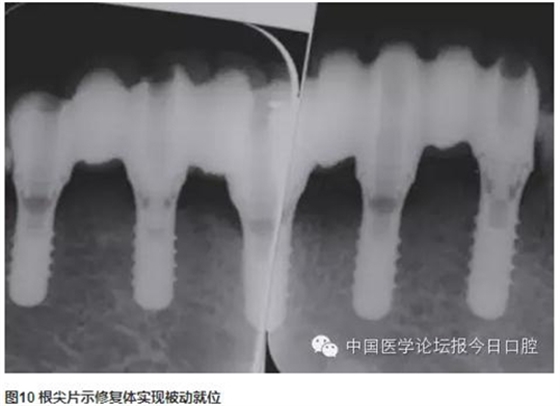

技工室制作純鈦支架,聚合瓷修復牙齒和牙齦形態(tài),患者口內(nèi)試戴,只將一個種植體的固定螺絲加力,拍片可見其余3顆種植體均實現(xiàn)被動就位,然后將4顆種植體固定螺絲加力,封口(圖2~圖10)。

曲面體層片示:種植體基臺與修復體密合性良好。1年后復診,支架無松動、折斷,中央螺絲未見折斷、松動,修復體未見崩瓷。種植體無松動,種植體周圍少量軟垢存,黏膜未見紅腫。種植體周圍探診深度:下頜左側(cè)尖牙(近中2mm、頰側(cè)3mm、遠中4mm、舌側(cè)2mm),下頜左側(cè)中切牙(近中2mm、頰側(cè)2mm、遠中4mm、舌側(cè)2mm),下頜右側(cè)側(cè)切牙(近中2mm、頰側(cè)2mm、遠中3mm、舌側(cè)3mm),下頜右側(cè)第一前磨牙(近中3mm、頰側(cè)2mm、遠中4mm、舌側(cè)3mm)(圖11~圖13)。

下頜多牙連續(xù)缺失,采用CAD/CAM純鈦支架聚合瓷固定修復,修復體精度高,與種植體密合性好,容易實現(xiàn)被動就位,聚合瓷牙齒、牙齦色較易恢復。